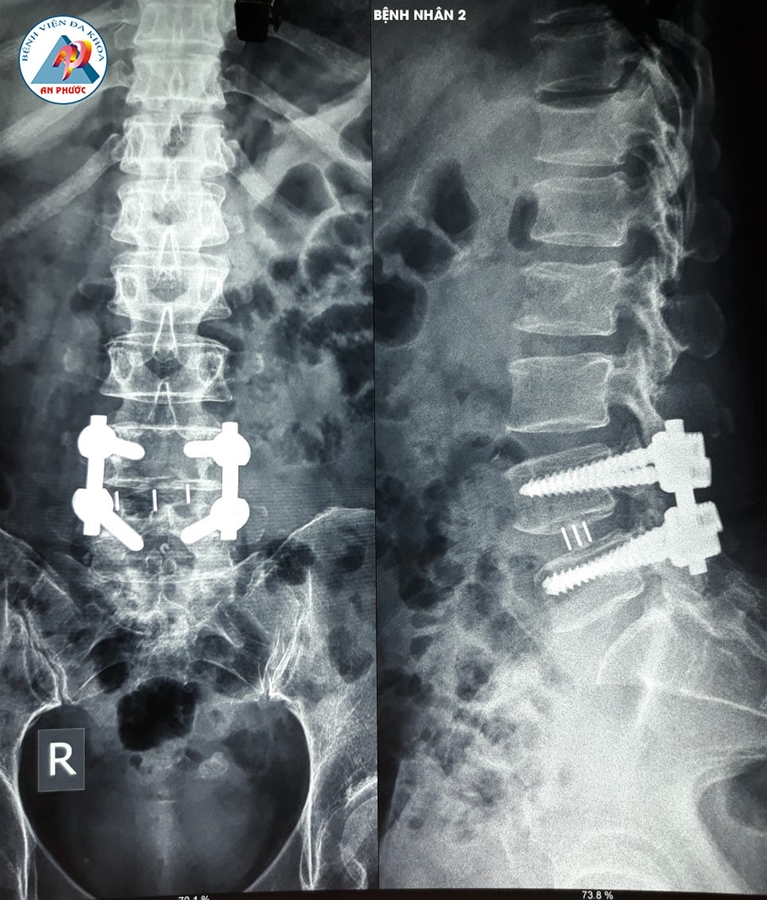

Trường hợp 1: Bệnh nhân nữ, 58 tuổi, ngụ tại Hàm Thuận Nam, Bình Thuận. Vào viện trong tình trạng đau lưng, tê, yếu hai chân hơn 10 năm. Bệnh nhân đã được điều trị nội khoa, kết hợp với tập vật lý trị liệu nhiều lần, ở nhiều Bệnh viện khác nhau, nhưng bệnh không giảm.

Sau khi được Bác sĩ chuyên khoa khám lâm sàng và cận lâm sàng (chụp MRI, XQ CSTL (có Film). Bệnh nhân được chỉ định phẫu thuật: Lấy nhân đệm và làm cứng CSTL bằng nẹp vis, thay đĩa đệm nhân tạo.

Sau 07 ngày phẫu thuật, bệnh nhân hết tê hai chân. Đi, đứng, vận động hai chân bình thường.